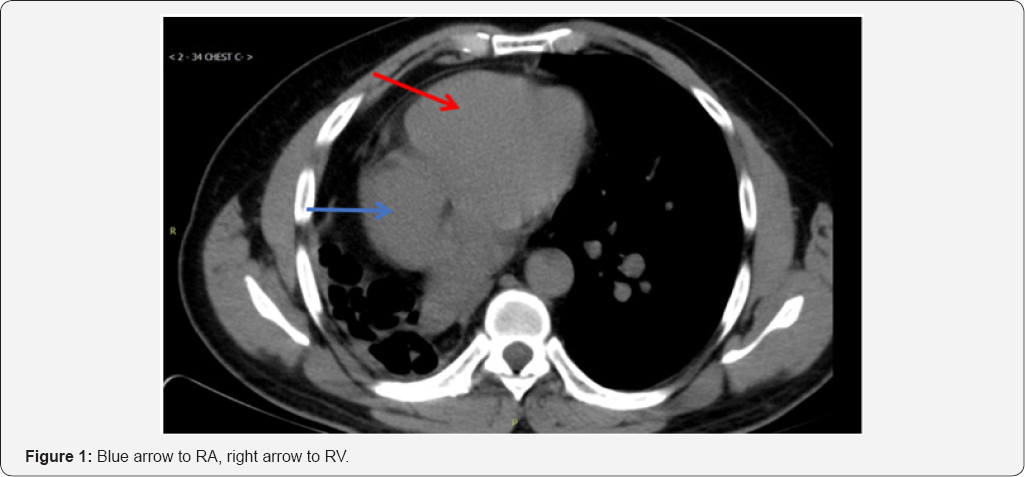

A CT scan of the thorax showed findings consistent with the post-pneumonectomy-like syndrome (Figure 1 & 2). Subsequent Pulmonary Function Tests: showed severe airway obstruction, without response to bronchodilators and severely decreased total lung capacity and diffusing capacity, EKG: sinus rhythm.

The patient was taken to the cardiac cath lab for implantation of a permanent pacemaker. Right ventricular (RV) lead placement was as follows: venous access was through cephalic vein dissection. Fluoroscopy images showed that the patient's heart was displaced to the right, which made it impossible to advance the RV lead into the right ventricle despite multiple attempts with different manually curved stylets. 9Fr coronary sinus (CS) delivery system (Biotronik -Selectra Extended Hook 45cm, model number 375527) was used to get into the RV over Terumo glide wire. The ventricular lead was next introduced through the 9Fr long CS sheath and positioned into the right ventricular lower septum. Following this procedure, the permanent pacemaker was successfully placed (Figure 3).